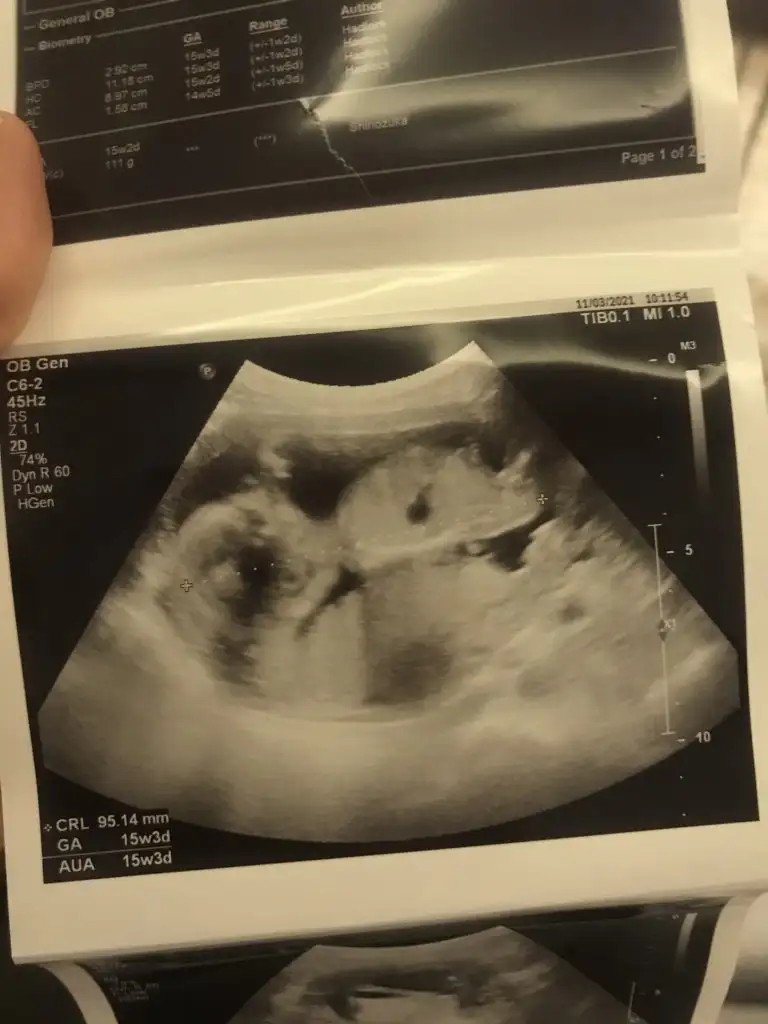

En iyi 11 12 13 haftalar olmalıIkra meyra kardeşimin 19 haftalik doktor söylemedi anlaşılıyor mu cinsiyeti

Erkek sanki en iyi 11 12 13 haftalar olmalıIkra meyra yorum yapar mısın?